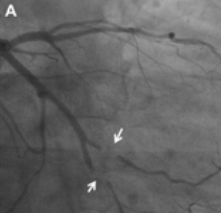

c.造影显示血管病变。如果造影显示血管狭窄到一定程度,医生会建议您做球囊扩张或支架植入术。